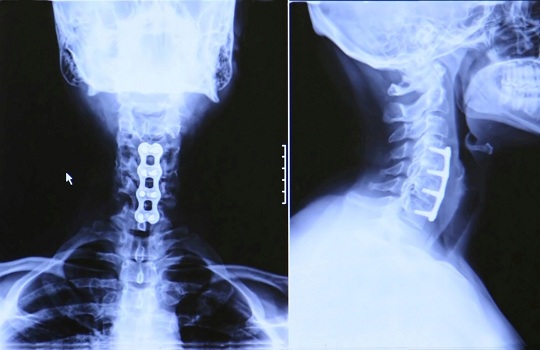

Anterior Cervical Discectomy Fusion And Metal Plate

Cervical Degenerative Disc Disease (wear and tear on the disc(s) Relief of Symptoms - Degenerative disc and joint disease of the neck will worsen with time, Anterior Cervical Discectomy Fusion and Metal Plate Author: ... Retrieve Here